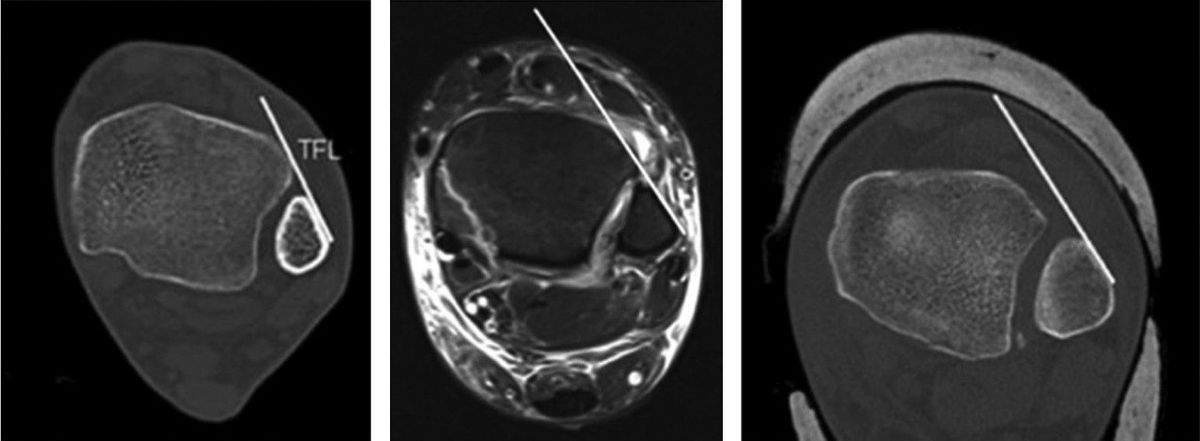

Рис. 14. Положение малоберцовой кости в боковой проекции

КТ превосходит стандартную рентгенографию в оценке целостности синдесмоза и способна выявлять подвывих синдесмоза, которую сложно визуализировать на обзорных рентгенограммах, особенно в неочевидных случаях. Возможность оценки обоих голеностопных суставов делает КТ предпочтительным неинвазивным методом оценки репозиции синдесмоза.

КТ-сканирование синдесмоза обычно проводится на уровне наиболее выступающей точки переднего бугорка большеберцовой кости. Повреждение синдесмоза диагностируется при межберцовом промежутке более 6 мм или расширении более 2 мм по сравнению с контралатеральной стороной. Повреждение с расхождением 2–3 мм может быть подтверждено на фронтальных КТ-срезах.

Рис. 15. Тибиофибулярная линия Гиффорда (TFL) на аксиальных срезах КТ и МРТ. Линия проводится вдоль переднелатеральной кортикальной поверхности малоберцовой кости. Расстояние от переднего бугорка Тилло-Шапута до TFL не должно превышать 2 мм. Параметр чувствителен к ротационной нестабильности.

КТ с нагрузкой (weight-bearing CT, WBCT) обладает дополнительным преимуществом — динамической оценкой синдесмоза: при нагрузке выявляются значимые латеральная трансляция и наружная ротация малоберцовой кости относительно вырезки.

В последние годы WBCT стала ведущим инструментом диагностики субклинической (subtle) нестабильности синдесмоза — той, которую не удаётся выявить стандартными методами. Наиболее перспективным направлением является трёхмерный волюметрический анализ: объёмные измерения синдесмоза на протяжении 5 см проксимальнее плафона большеберцовой кости продемонстрировали площадь под ROC-кривой 0,96 с чувствительностью 90% и специфичностью 95% (Ashkani Esfahani et al., 2022). Трёхмерное картирование расстояний (3D distance mapping) на WBCT показало наибольшую диагностическую точность в первых 1–3 см вырезки с AUC 80,9–83,0% (Krähenbühl et al., 2025). Эти данные свидетельствуют о том, что 3D-волюметрия на WBCT может стать новым стандартом диагностики повреждений синдесмоза, особенно в клинически неоднозначных ситуациях.